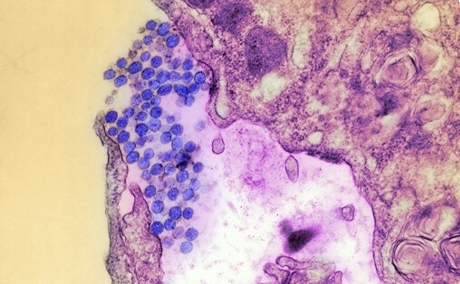

Возбудитель ГЛПС – вирус, был выделен южнокорейским ученым H.W.Lee из легких грызуна. Вирус получил название Hantaan (по названию реки Хантаан, протекающей на Корейском полуострове). Позднее такие вирусы обнаруживались во многих странах — в Финляндии, США, России, КНР и в других. Возбудитель ГЛПС отнесен к семейству буньявирусов (Bunyaviridae) и выделен в отдельный род, который включает несколько сероваров: вирус Puumala, циркулирующий в Европе (эпидемическая нефропатия), вирус Dubrava (на Балканах) и вирус Seul (распространен на всех континентах). Это РНК-содержащие вирусы до 110 нм в размерах, погибают при температуре 50°С в течение 30 минут, а при 0-4°С (температура бытового холодильника) сохраняются 12 ч.

Вирус Хантаан — возбудитель ГЛПС

Особенность вируса Хантаан: склонность поражать эндотелий (внутреннюю оболочку) кровеносных сосудов.